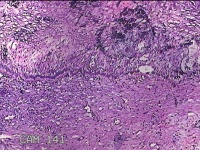

宫颈锥切物

女

31岁

宫颈上皮内瘤变

妇检发现宫颈CIN2 2个月。

灰白暗红色组织2.8x1.8x0.3cm一块,表面糜烂,切面灰白暗红色,质软。

所提供图片不具有诊断价值。

为什么不拍鳞状上皮呢?